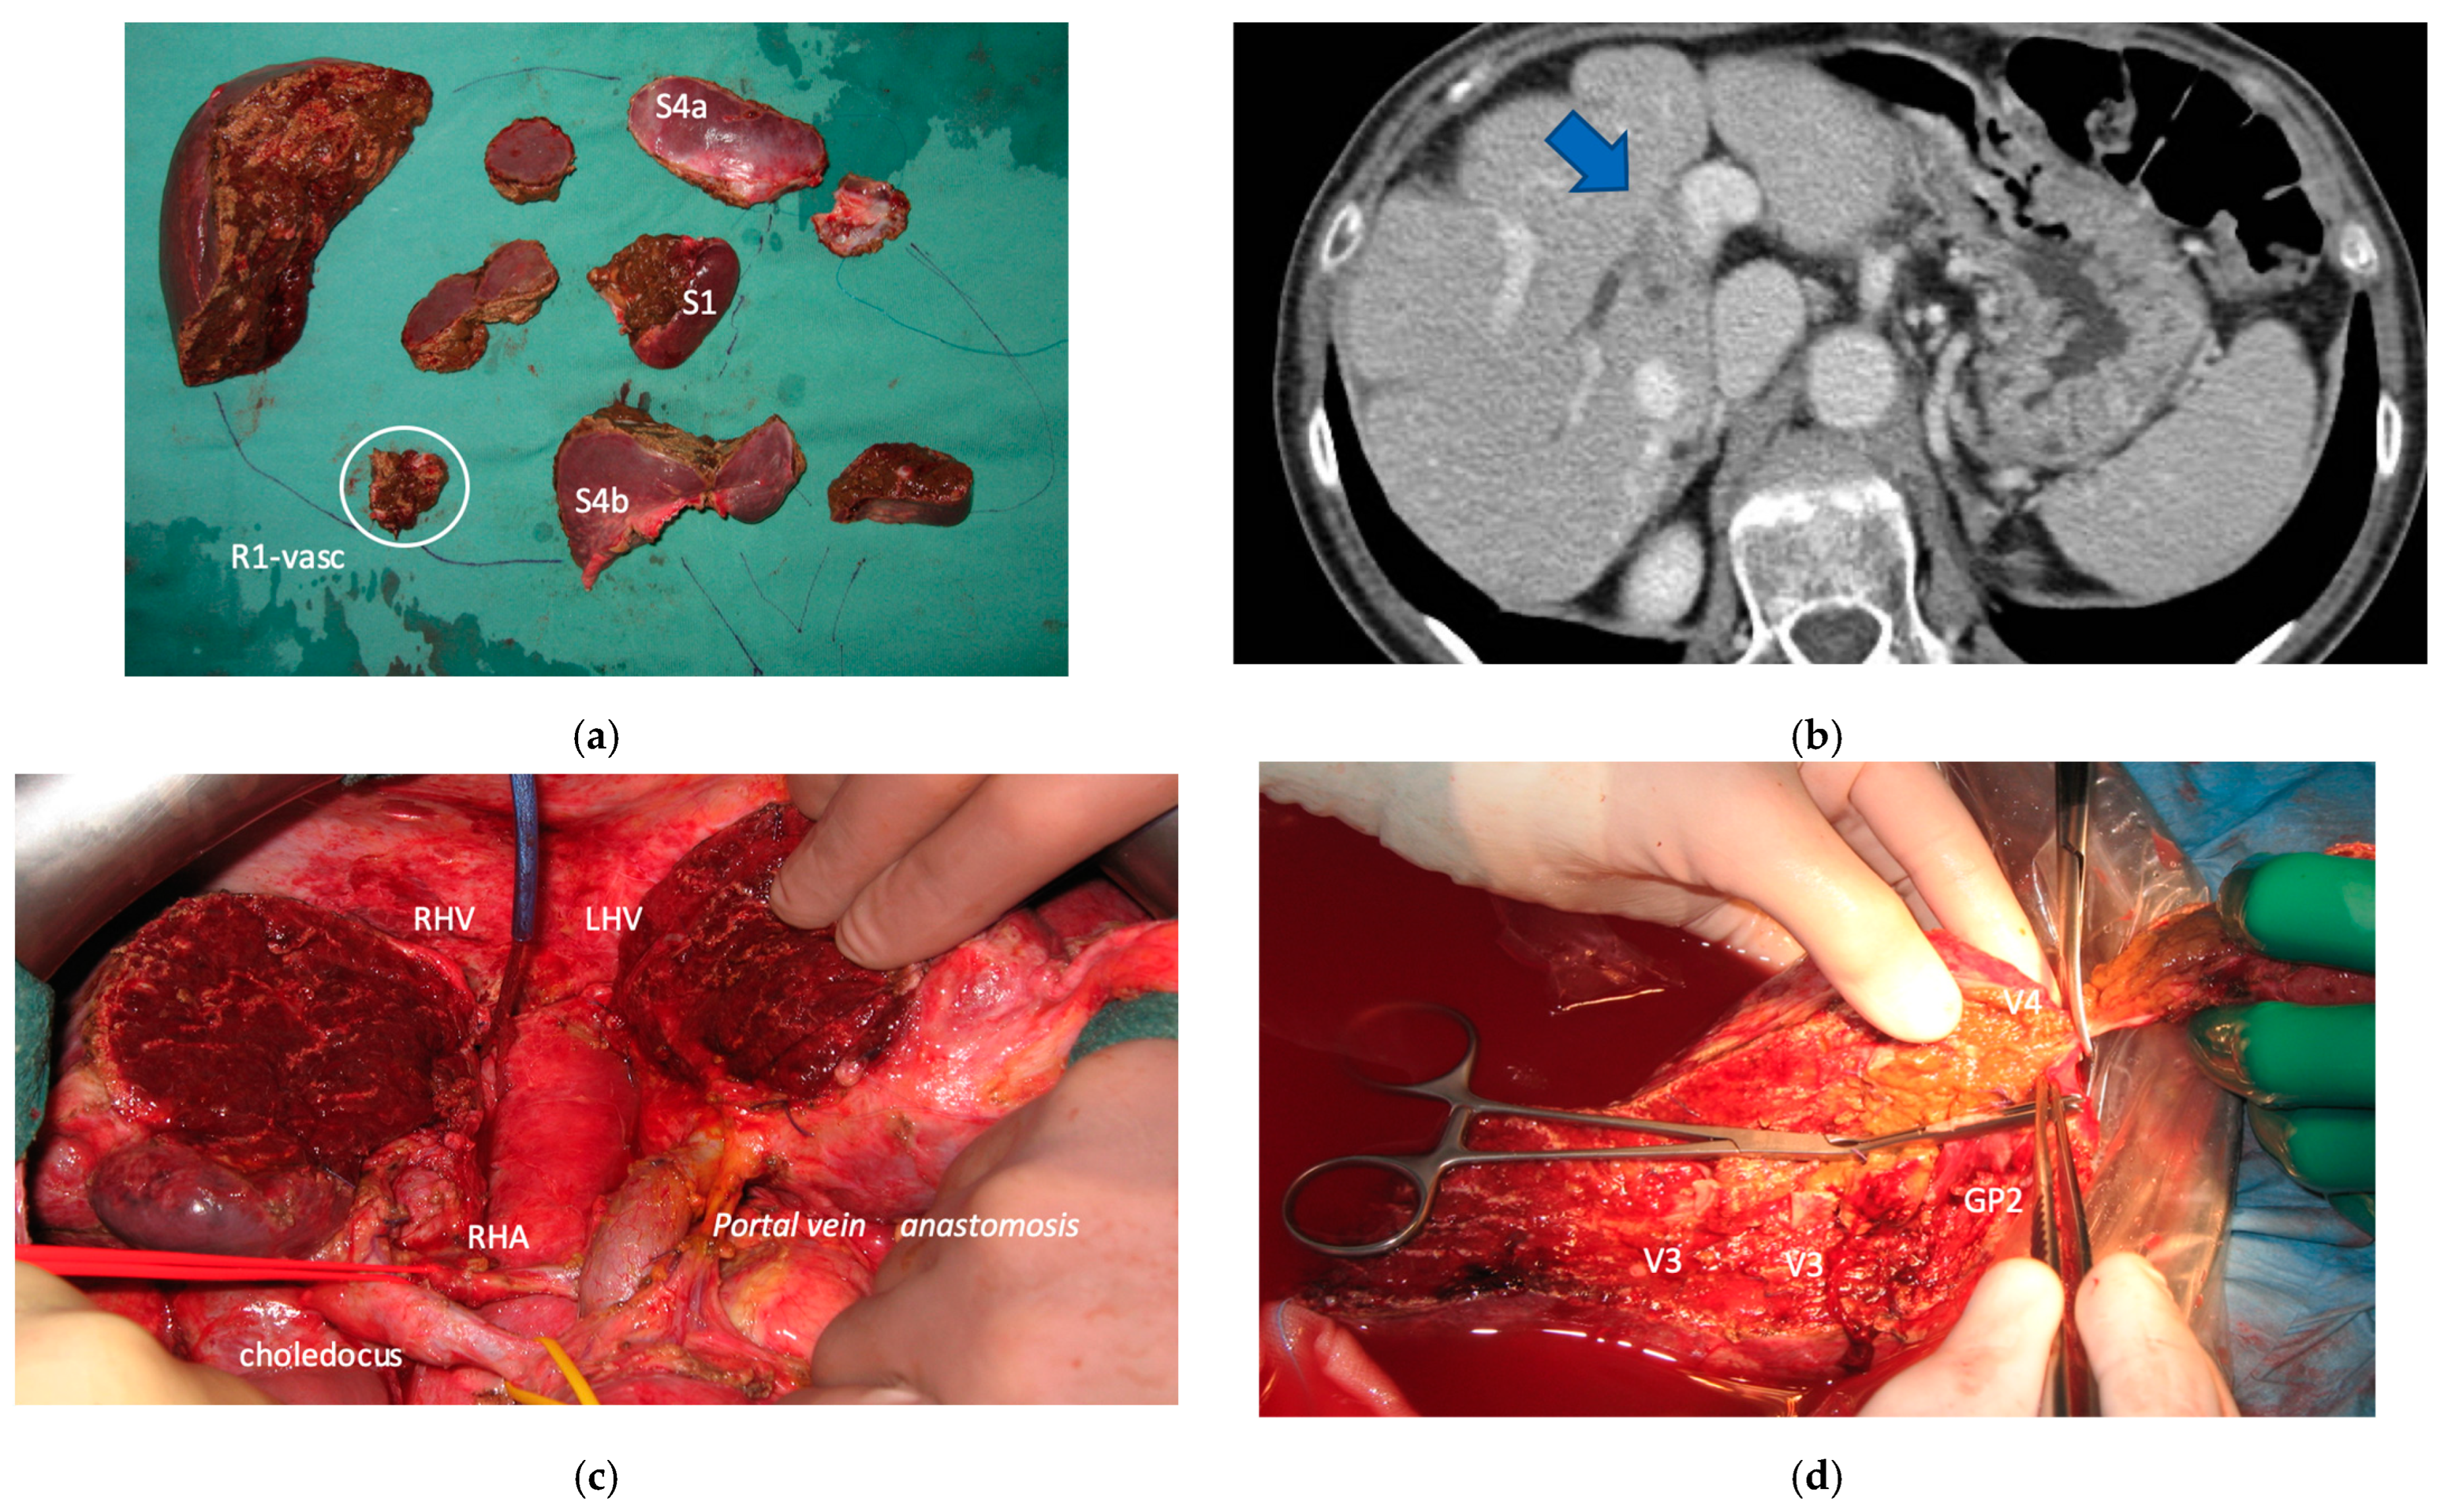

3.3. PS-TSH with SS-PVE

Super-selective portal vein embolization was performed in three patients since the resection of first-order GPs was deemed not necessary and a TWO-STAGE major PSH with SS-PVE was planned. Percutaneous PVE was achieved under US guidance via an ipsilateral approach through the tumor-bearing liver in two patients and via a contralateral approach through the future remnant liver in one patient. The accesses were respectively by S6, S5 and S3 portal vein branches under US guidance and local anesthesia. In all three cases S1/S4 were anatomically resected en-bloc with MHV at the first stage (MLP). Super-selective PVE consisted in embolization of portal branch for S6/S7/S8 in one case, for S7/S8 in one case and for S5/S8 in one case. The second stage was performed 58, 57 and 63 days after the first stage and consisted in the resection of S6/S7/S8 with RHV skeletonization in one case (see Figure 6 and Figure 7), in resection of S7/S8 partially extended to S5/S6 en-bloc with RHV reconstructed with an end-to-end anastomosis in one case (see Figure 8) and in resection of S7/S8/S5 en-bloc with RHV reconstructed with end-to-end anastomosis in another case. No complications occurred after surgery and patients were discharged from the hospital on the 11th, 11th and 17th post-operative day. The primary was resected at the time of the first stage (right hemicolectomy) in two cases and before the first stage (left hemicolectomy, “primary first” strategy) in one case.

Figure 6. CT Images of PS-TSH with SS-PVE performed to treat 35 bilateral CRLMs. (a) Partial response after FOLFOXIRI + Bevacizumab 12 cycles; FLR (=S2/S3) volume is 15%. (b) Blue arrow points GP 5 after the first stage consisting of resection of S1/S4 extended to S2/S8/S5 plus metastasectomy of S2 with tangential resection of LHV. (c) Fourteen days after stage 1 SS-PVE was performed on the right liver preserving GP 5 (blue arrow); 37 days after SS-PVE FLR (=S2/S3/S5) increased up to 37%. (d) Blue arrow points GP 5. Twenty-five months after PS-TSH with SS-PVE the patient is disease free; the liver’s only disease recurrence was successfully treated with another 3 liver resections (2 on the right liver and 1 on the left). Abbreviations: PS-TSH: parenchyma-sparing TWO-STAGE hepatectomy; SS-PVE: super-selective portal vein embolization; CRLM: colorectal liver metastases; FLR: future liver remnant; S: segment; GP5: glissonean pedicle for segment 5; LHV: left hepatic vein.

Cancers 15 04683 g006

Figure 7. Intraoperative field images of PS-TSH with SS-PVE performed to treat 35 bilateral CRLMs. (a) Hole liver at the first stage after FOLFOXIRI + Bevacizumab 12 cycles, with liver transection lines (yellow dotted lines). (b) At the end of the first stage of TS-PSH with SS-PVE: resection of S1/S4 extended to S2/S8/S5 plus metastasectomy of S2 with tangential resection of LHV, first-order GPs are completely exposed; the primary is resected with a simultaneous right hemicolectomy. (c) At the end of the second stage performed 58 days after the first stage, embolized liver is completely resected and S5 only is preserved, the left liver remains untouched. (d) At the second stage S5 was twisted to avoid kinking of RHV which is completely skeletonized, for this reason GPs 6–7 and GP 8 appear inverted. Abbreviations: PS-TSH: parenchyma-sparing TWO-STAGE hepatectomy; SS-PVE: super-selective portal vein embolization; CRLM: colorectal liver metastases; RHV: right hepatic vein; LHV: left hepatic vein; V4: scissural hepatic vein; S: segment; GP: glissonean pedicle; UP: umbilical portion.